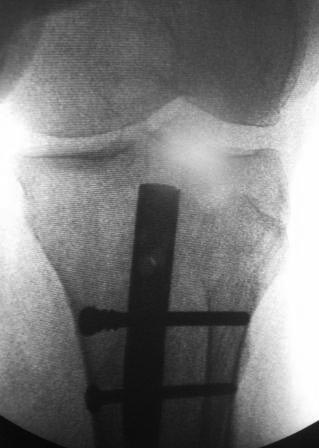

Здравствуйте, уважаемые коллеги! Всем огромное спасибо! Сегодня

оперировали, косая остеотомия н/з малоберцовой кости, открыть зона л/с,

как правильно заметили л/с оказалась не тугая, вообще нет сращения,

интерпозиция м/тканями, к/м канал закрыть частично, сильнейший

остеопороз , даже однозубым крючком всё ломается, экономная резекция

концов, укорочение было 1,5см, стало 3см, дефект заполнили аутографтом,

учитывая что винты не держат пластину не ставили, БИОС реконструктивным

стержнем, дистально 4 винта, два из них через аутокость и оба отломка,

получилось не очень стабильно,  но вроде держится хорошо.

Стержень чуть ушел кнаружу и кпереди--не знаю,  это плохо? Дальше для

стабилизации нужна ли временная внешная иммобилизация?